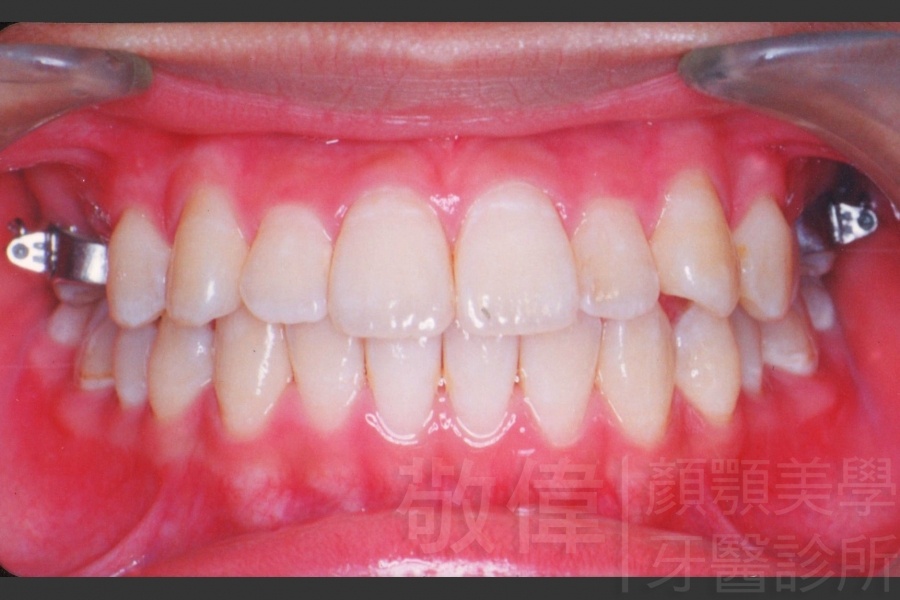

變臉矯正,原來戽斗妹跟大歪臉變成自信正妹

經由本院3D數影X光影像儀分析、與3D齒顎顏矯正技術,再配合口腔顎面正顎專科醫師施以正顎手術治療,雙方共同合作,使患者臉部外觀有很好的改善,大歪變小歪,產生了天南地北的大改變,她的人生也整個變得不一樣。

因為矯正與正顎手術的配合,使「戽斗妹」變成了「陽光正妹」,完全的改變了她的人生,在面對各種場合、與人交際都散發出自信微笑。所以,奉勸家長,如果小朋友有臉顎畸型的問題,應該考慮配合做這種簡單、安全、有效的正顎手術。